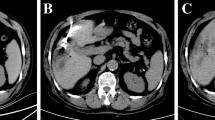

Example of a hypervascular hepatocellular carcinoma (HCC) ablation. A. Digital subtraction angiography of the right hepatic artery shows three hypervascular HCCs. B. C-arm CT with hepatic arteriography shows the first target lesion. C. Antenna in position. D and E. Fused pre- and post-ablation C-arm CTs depicting ablation margins

Example of a colorectal liver metastasis ablation. A. Solitary colorectal cancer liver metastasis only visible on diffusion weighted MRI (not visible on contrast-enhanced MRI). B. C-arm CT with hepatic arteriography clearly depicts the 11 mm lesion. C. Planning of trajectory. D. Ablation zone depicted with C-arm CT hepatic arteriography directly after ablation for 8 min at 120W. E and F. Fused pre- and post-ablation C-arm CTs in axial and coronal view show adequate margins

Overall, the enhanced visibility and advanced navigation options afforded by the method have expanded the scope of treatable lesions and allowed for treatment of lesions previously considered non-ablatable. Notably, deeply seated lesions or small lesions detectable only as diffusion restriction foci on MRI (and invisible on other MRI sequences, CT or ultrasound) can now be visualized and ablated with this technique.

While primarily effective for hypervascular tumors, this technique also demonstrated success in hypovascular tumors. In practice, most tumors that appeared hypovascular on CT or MRI showed arterial hyperenhancement on hepatic arteriography C-arm CT. However, within this cohort, two small hypovascular colorectal metastases could not be clearly identified on hepatic arteriography C-arm CT. Therefore, an optional delayed phase C-arm protocol (40 s delay) was added that enabled the identification of tumors without any arterially enhancing component.